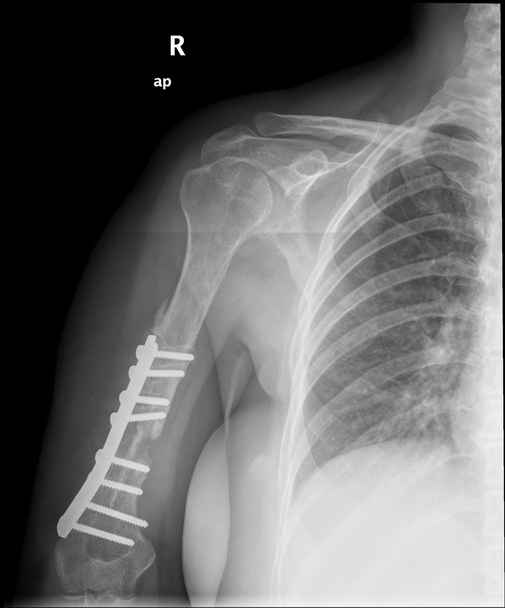

Больная 48 лет, медсестра-массажист, перелом плеча 7 лет назад, оперирована 4-кратно и безуспешно

Больная 48 лет, медсестра. Травма получена 7 лет назад, оперирована первично в Турции - остеосинтез пластиной - несращение - реостеосинтез стержнем там же через год (обычным, с выстоянеием его в полость плеча) - несращение - поступила к нам впервые в марте 2008 года - удаление стержня, реостеосинтез пластиной и костная пластика, в течение 2 лет лизис кости вокруг винтов, смещение фиксатора, в марте 2010 - удаление пластины, реостеосинтез интрамедуллярным стержнем с блокированием (рассверливание + костная пластика). В динамике - вновь лизис в области перелома, нестабильность дистальных блокирующих винтов.

Клинически фиксация пока действительно стабильна, но на рентгенограммах резорбция кости в области дистальных блокирующих винтов и миграция одного из них.